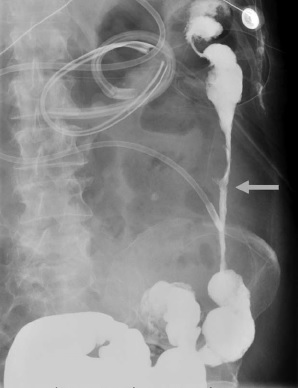

Une sténose inflammatoire (Fig. 2) a été diagnostiquée chez 7 patients. Pendant le traitement, cela s’est avéré efficace chez chacun d’eux. Le côlon gauche était atteint chez 4 patients et le côlon droit chez 3 patients. Cinq patients ont développé une obstruction colique nécessitant une colectomie et un débridement pancréatique ouvert concomitant.

Sténose inflammatoire développée après la mise en place d’un drain percutané chez 1 patient et après débridement pancréatique ouvert chez 1 patient. Dans tous les cas, l’imagerie préopératoire montrait une nécrose péripancréatique entourant le segment colique impliqué.

Figure 2 : Lavement baryté démontrant une sténose inflammatoire de 11 cm au niveau du côlon descendant (flèche), chez un patient atteint de pancréatite nécrosante